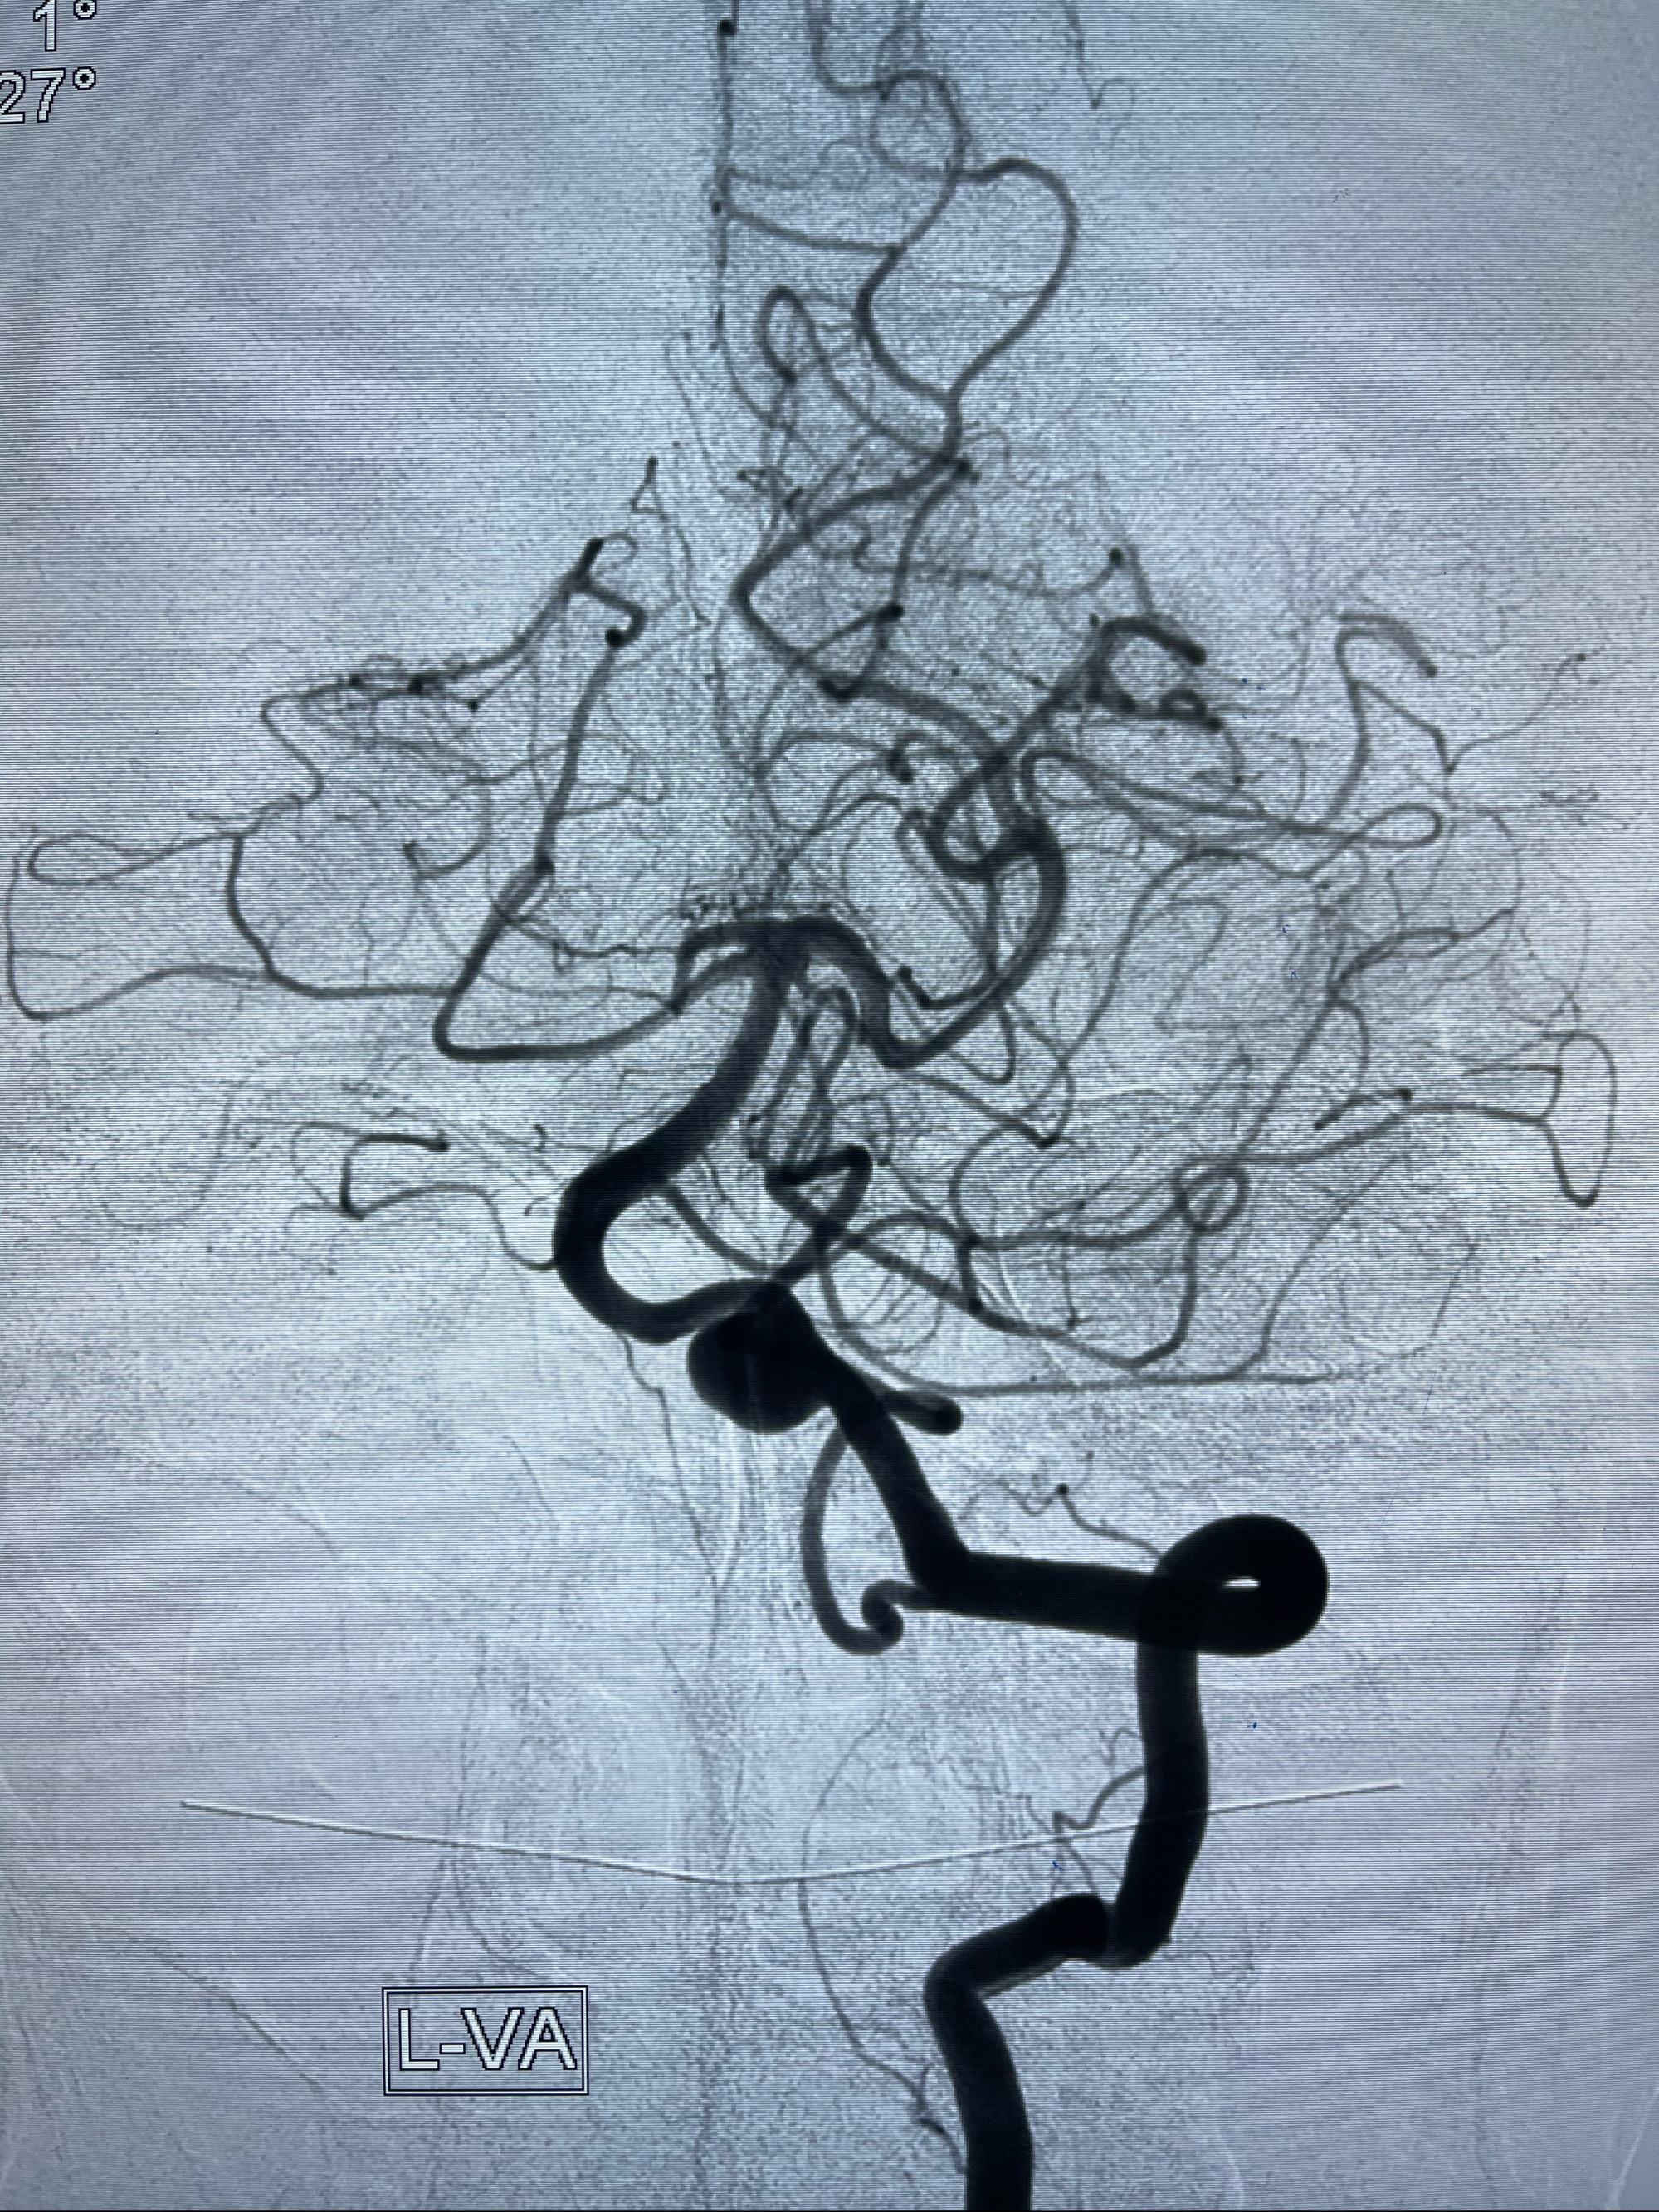

左侧椎动脉V4夹层动脉瘤多支架辅助栓塞:

工作角度造影